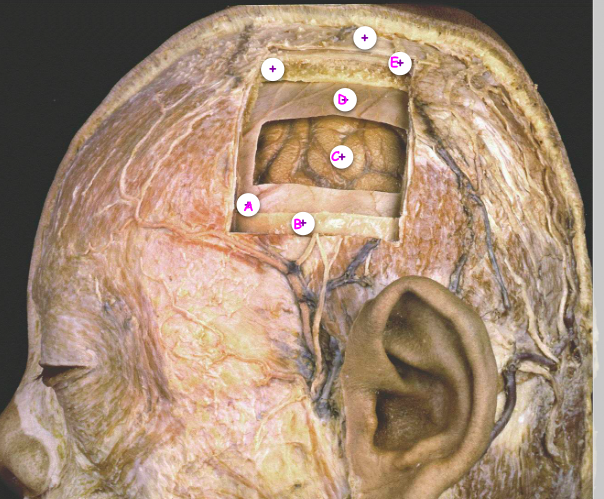

Q

Which of the following is the periosteum

A

B

C

D

E

Which of the following is the middle meningeal vessel

Which of the following is the arachnoid mater